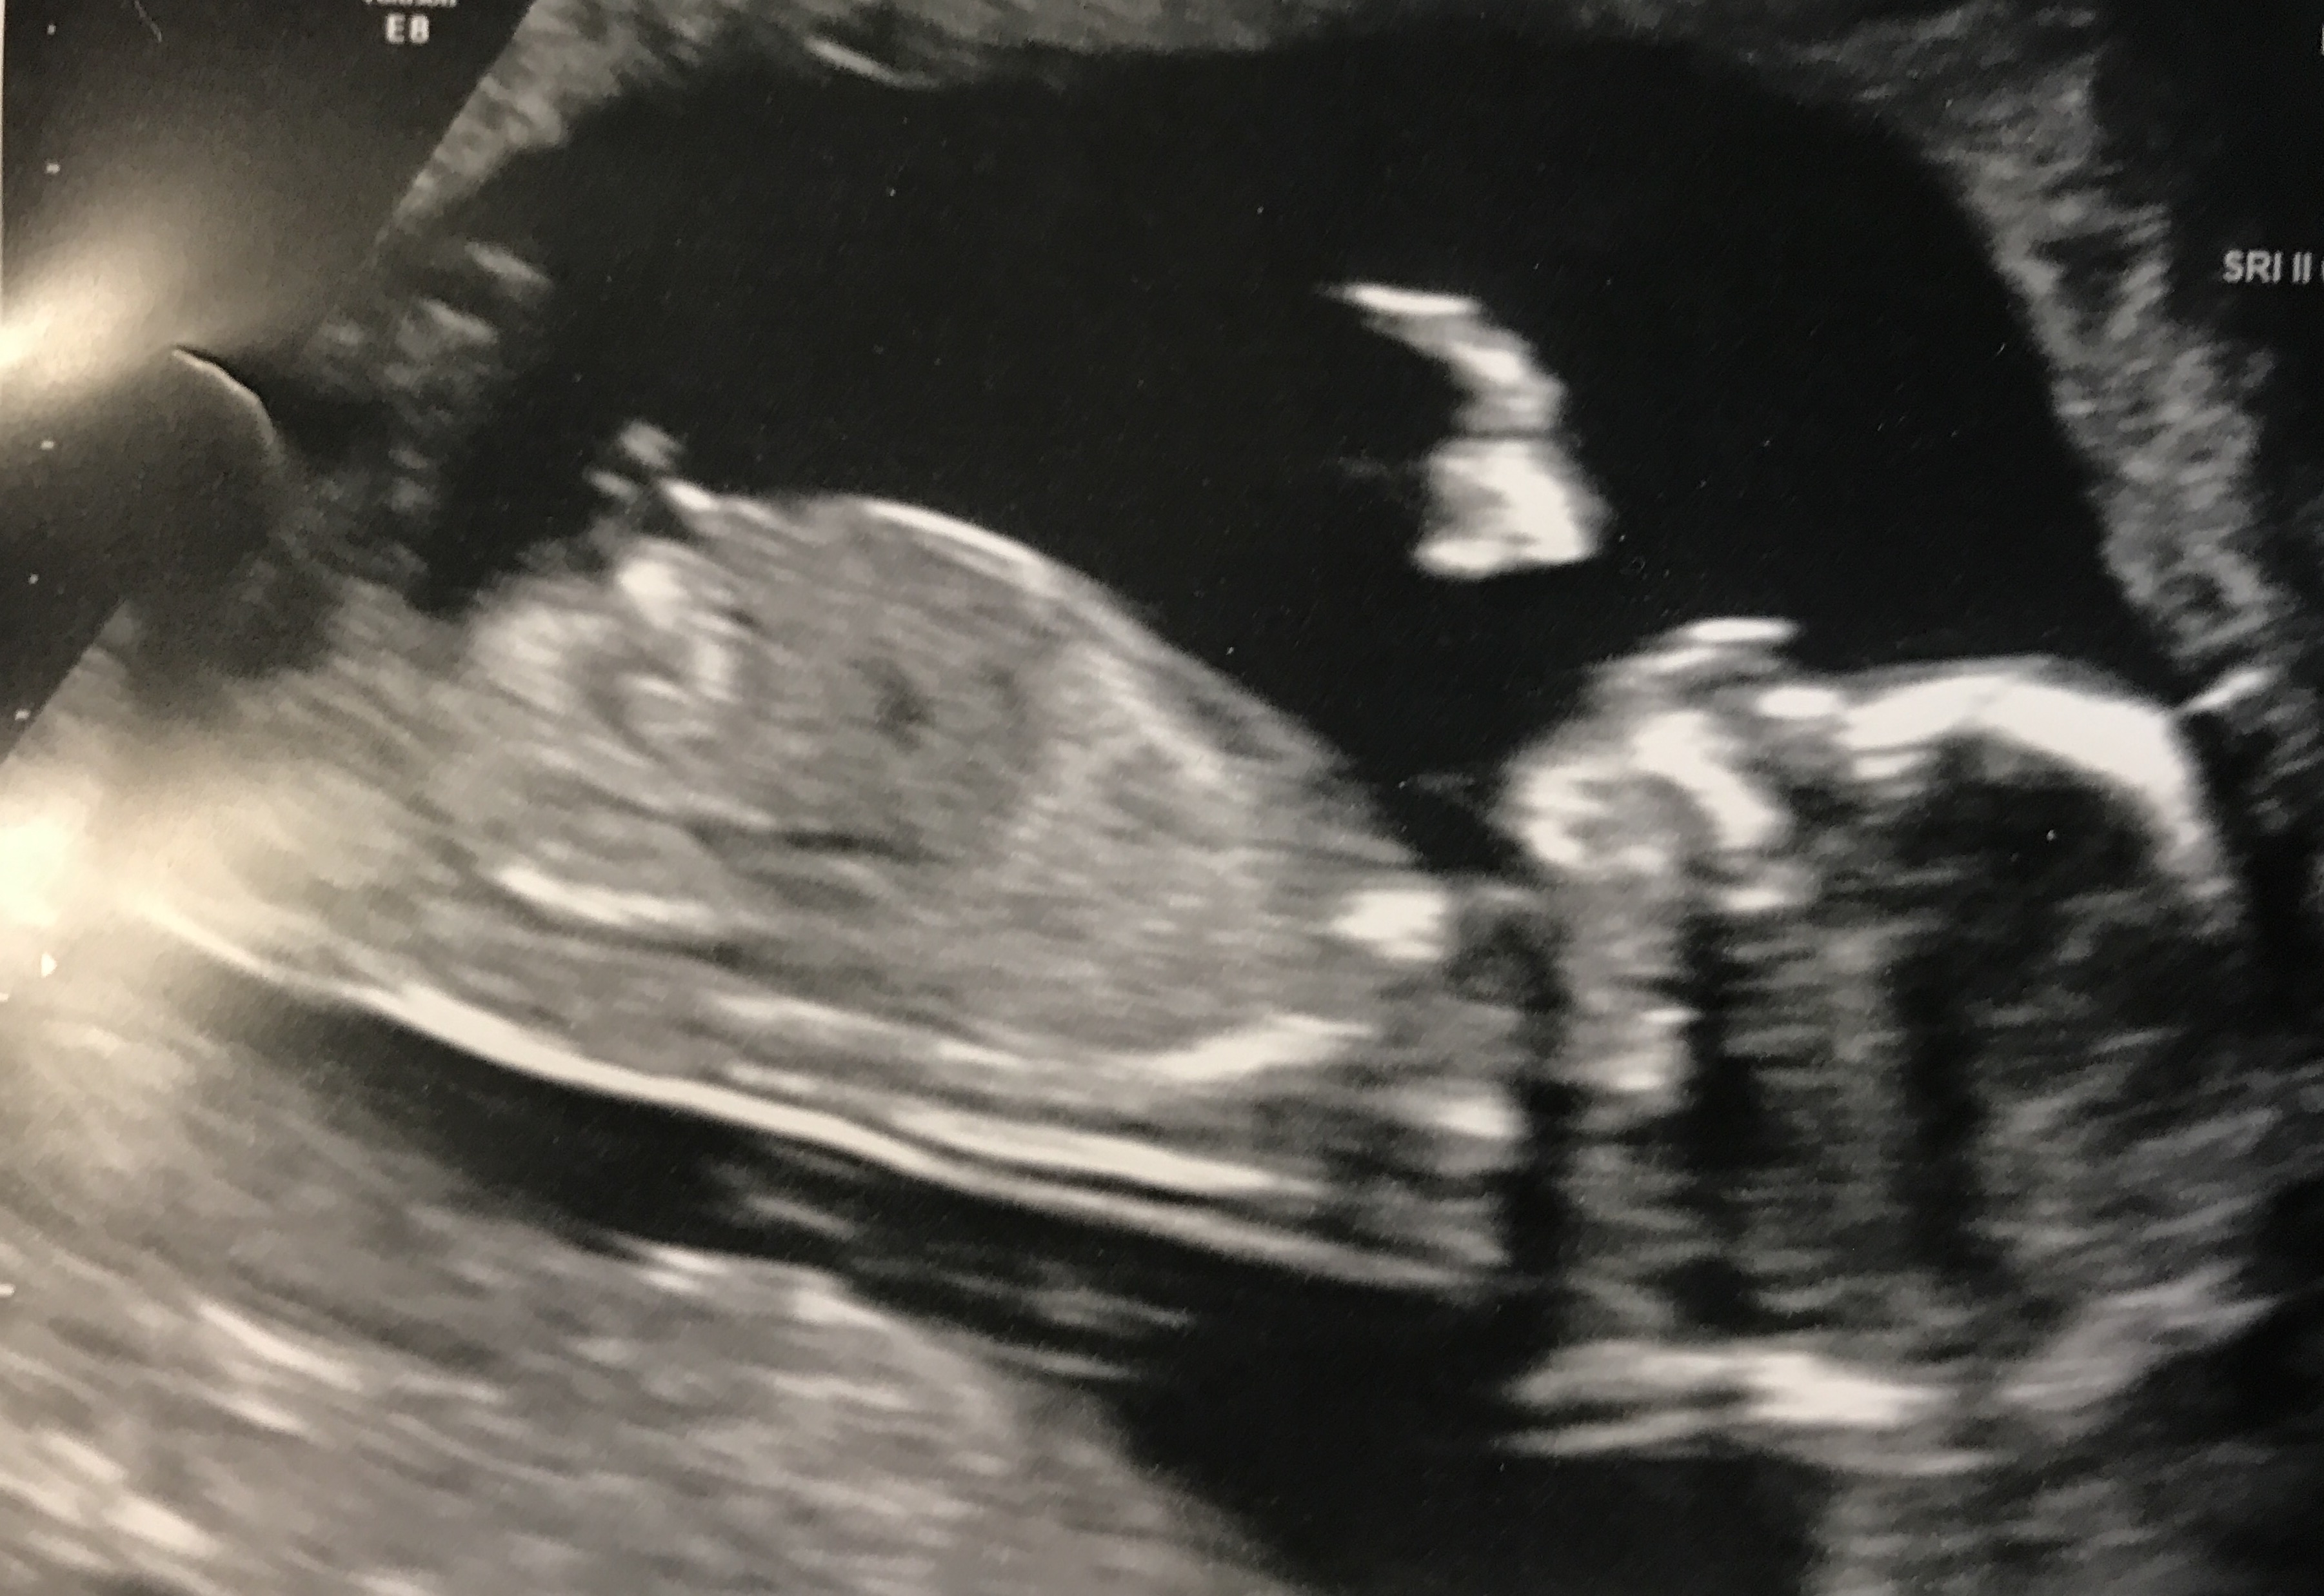

I finally found the correct forum to post this thread! ;) Any guesses greatly appreciated! Thanks!!Attachment 36504

Not sure if nub is properly showing, but guessing girl for now. Any more pics?